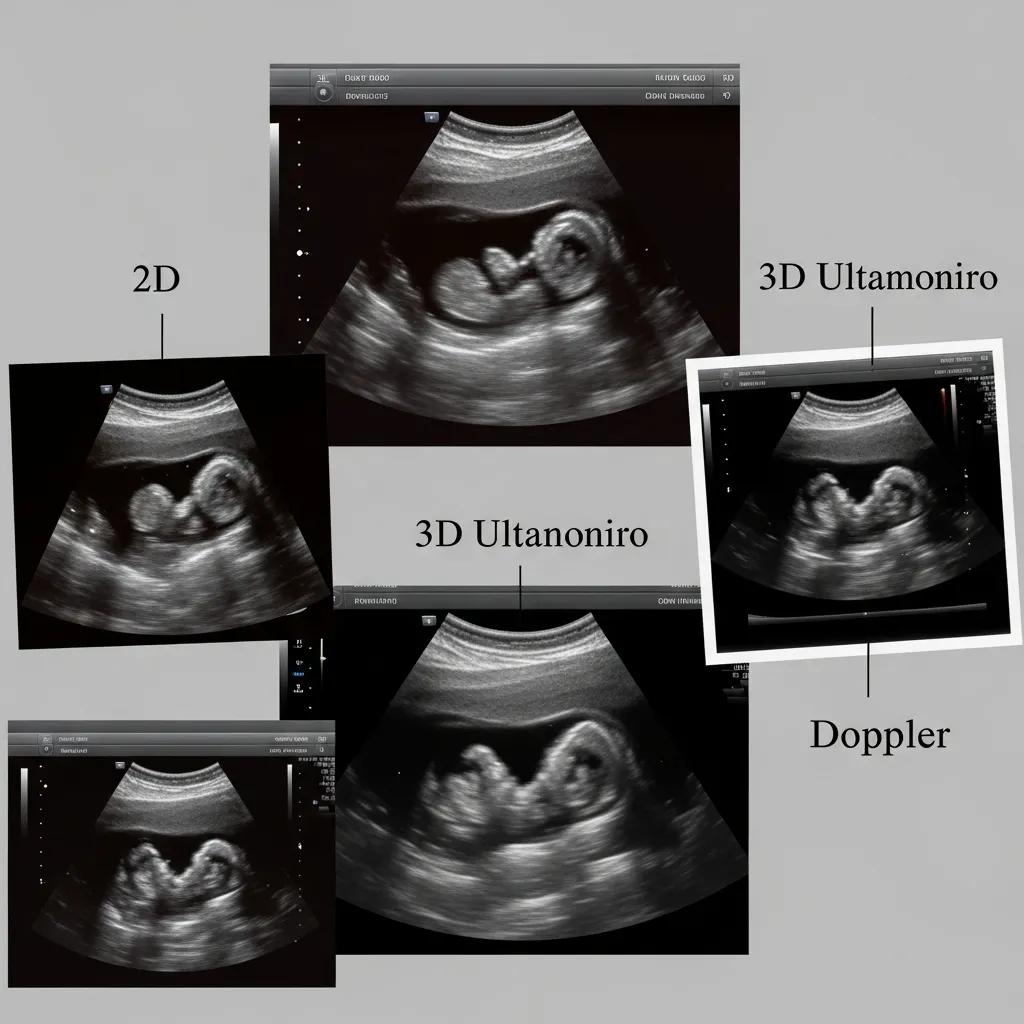

What Are the Common Types of Pregnancy Ultrasound Scans?

There are several types of pregnancy ultrasound scans, each serving a specific purpose. Understanding these types can help expecting mothers know what to expect during their appointments.

| Scan Type | Description | Timing |

|---|---|---|

| 2D Ultrasound | Provides flat images of the fetus, commonly used for routine checks. | Typically performed in the first and second trimesters. |

| 3D Ultrasound | Creates three-dimensional images, offering a more detailed view of the fetus. | Often done in the second or third trimester. |

| Doppler Ultrasound | Measures blood flow in the fetus and placenta, assessing fetal health. | Usually performed in the second or third trimester. |

These scans are essential for monitoring fetal health and development, allowing healthcare providers to make informed decisions regarding prenatal care.